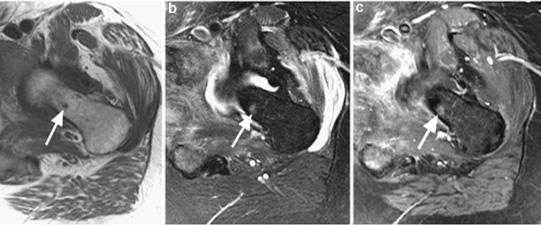

Инфильтративно растущие опухоли мочевого пузыря.

а) Т2 cor FS б) Т2-tra

Женщина, 56 лет. Клинически – гематурия, морфологически верифицированная опухоль мочевого пузыря. На представленных бесконтрастных Т2-взвешенных изображениях в корональной (а) и аксиальной (б) плоскостях видно асимметричное инфильтративное утолщение левой стеки мочевого пузыря, ригидность и уплощение левой стенки на фоне нормального наполнения пузыря. При этом наружный контур инфильтративно утолщенной стенки имеет нечеткие контуры.

Внутривенное динамическое контрастирование, Т1-ВИ, ранняя (артериальная фаза). Видно выраженное диффузное контрастное усиление всей толщины инфильративно измененной левой (и частично задней) стенок мочевого пузыря, с нечеткостью ее наружного контура и признаками минимального экстравезикального распространения.